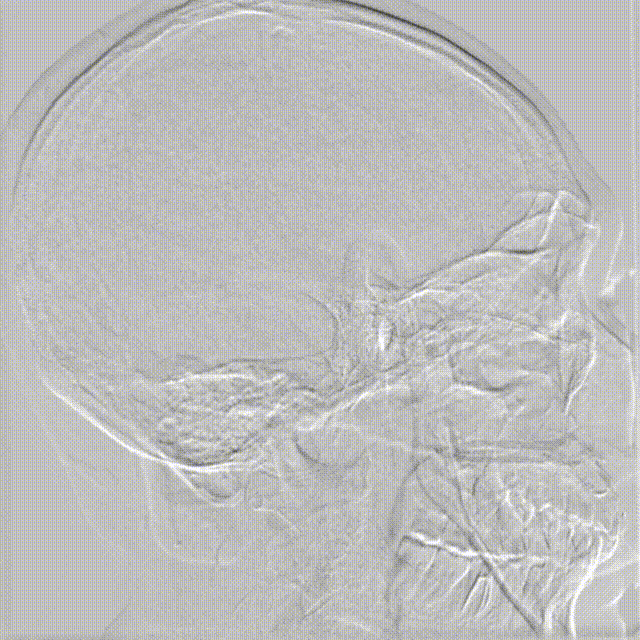

影像信息

术后6个月复查造影。